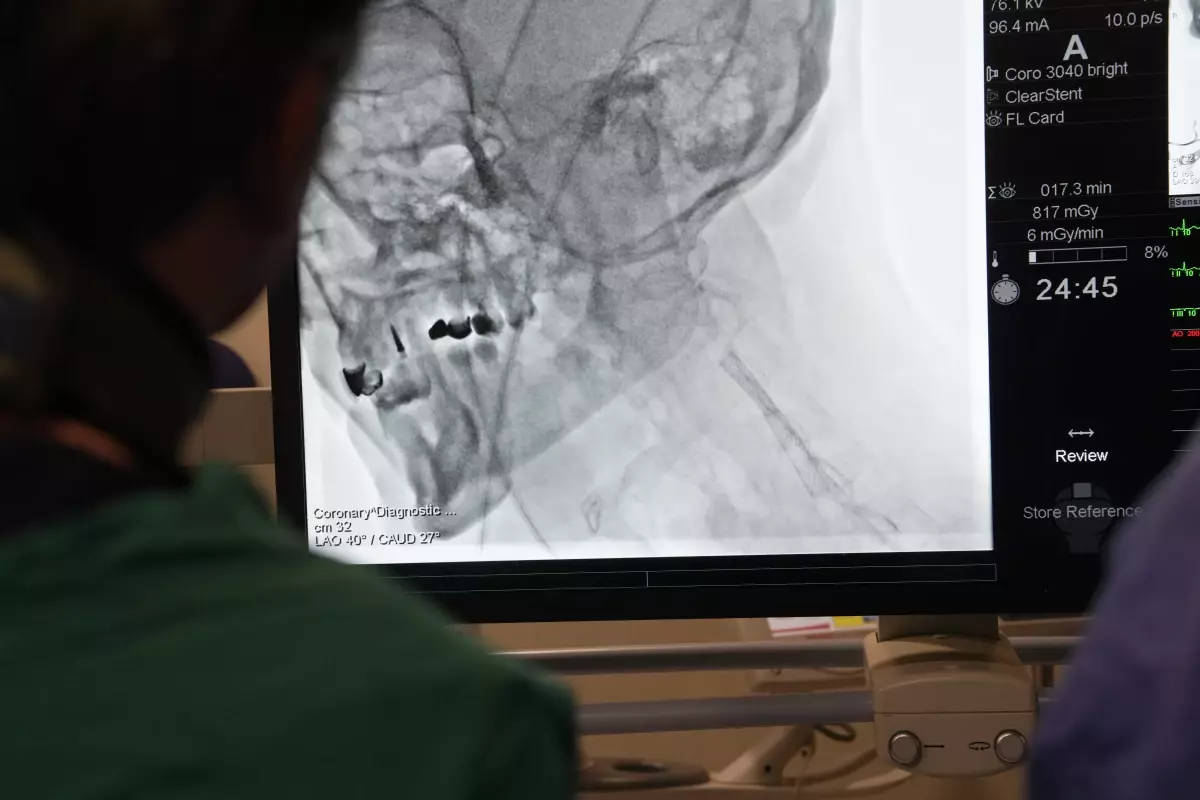

Kardiyoloji uzmanları, yurt dışından gelen doktorlara yönelik 'İleri Stent Teknikleri' ve 'Kronik Damar Açma' alanlarında eğitim verdi. Prof. Dr. Ertuğrul Okuyan öncülüğünde gerçekleşen eğitim sırasında teorik bilgilerin yanı sıra, canlı operasyonlarla betonlaşmış damarlar açıldı.

Medipol Sağlık Grubu'nun düzenlediği ve bugün başlayan program, Kardiyoloji Uzmanı Prof. Dr. Ertuğrul Okuyan liderliğinde gerçekleştiriliyor. Özellikle Mısır, Pakistan, Tunus ve Cezayir gibi ülkelerden gelen doktorlara modern tıp alanındaki yenilikler ve ileri teknikler aktarıldı. 'İleri Stent Teknikleri' ve 'Kronik Damar Açma' gibi uygulamalar tüm detaylarıyla paylaşılırken, katılımcılara hem teorik bilgiler hem de canlı operasyon deneyimleri sunuldu. Eğitimler yarın da devam edecek.

Prof. Dr. Okuyan, geleneksel yöntemlerle açılması mümkün olmayan damar tıkanıklıklarının, ileri teknikler sayesinde başarıyla tedavi edilebildiğini de söyleyerek, "Eskiden, çatallanma veya dallanma noktalarındaki darlıklar ya da uzun süredir tıkalı, betonlaşmış, kireçlenmiş damarlar açılamıyordu. Ancak günümüzde kullandığımız ileri teknikler sayesinde bu sorunların üstesinden geliyoruz" diye konuştu.

"Bu tekniklerin temelinde, damar içi ultrason gibi görüntüleme yöntemleriyle damar morfolojisinin detaylı bir şekilde incelenmesi ve özel cihazların yardımıyla tıkanıklıkların açılması yer alıyor" diyen Prof. Dr. Okuyan, "Damar içi tıraşlama yöntemleri, taşırma kateterleri ve özel malzemelerle artık eskiden açamadığımız damarları açabiliyoruz. Bu işlemler, ileri stentleme teknikleri olarak adlandırılıyor" ifadelerini kullandı.